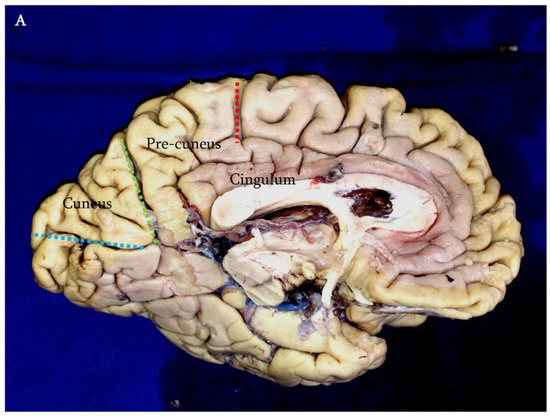

Figure 1.

Klingler’s technique; basal surface of the cerebral hemispheres after the removal of the fusiform gyrus and inferior longitudinal fasciculus. In this photograph, the relationships between the atrial cavity (a) and the white matter fibers of the region can be observed. The lateral wall of the atrium is entirely covered by the optic radiations (or). Medially, the splenial fibers (s) form the forceps major (fm). On the left side, note the ependymal veins identifying the atrial cavity (asterisk).

Surgical removal of tumors of the atrium is a challenge, even to the most seasoned neurosurgeons. The issues are related not only to the deep location of this portion of the lateral ventricles but also to the vascularization of lesions of this area and to their complex three-dimensional relationships with the highly functional white matter fibers of the region [1,2,3]. In fact, the lateral wall of the atrium is entirely covered by a complicated system of fibers known as the sagittal stratum, which includes the optic radiations and some contingents of parietopontine and occipitopontine fibers. The basal surface is covered by the inferior longitudinal fasciculus, whereas white matter fibers related to the medial surface are the cingulum and the forceps major [4,5,6,7,8,9] (Figure 1). Given the functional importance of these structures and the often-benign nature of the lesions involving this area, an efficient approach to the atrium should be able to combine a total resection with respect to the anatomo-functional integrity of the white matter fibers [10]. Bearing this concept in mind, several surgical approaches to the atrium have been proposed [4]. The ipsilateral interhemispheric transprecuneus (IITA) approach satisfies these requisites. In this work, we present a clinical series of patients affected by tumors of the atrium that were approached through this elegant and complicated route. A detailed description of the technical aspects of the approach and a comparison with the possible alternatives is also given.